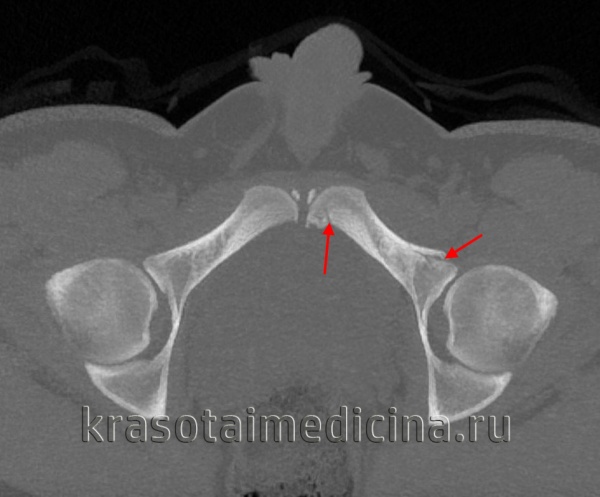

• КТ позволяет отличить между собой переломы колонн, поперечный перелом и Т-образные переломы:

о Перелом колонны: линия перелома проходит через вертлужную впадину в коронарном срезе

о Поперечный или Т-образный перелом: линия перелома проходит сквозь вертлужную впадину на сагиттальном срезе

(Слева) КТ, 3D реконструкция подвздошной проекции Жюде: определяется изолированный перелом крыла подвздошной кости (Дювернье) вследствие удара о дерево при катании на лыжах. Несмотря на распространение перелома в соседнюю губу вертлужной впадины, повреждение сустава отсутствует.